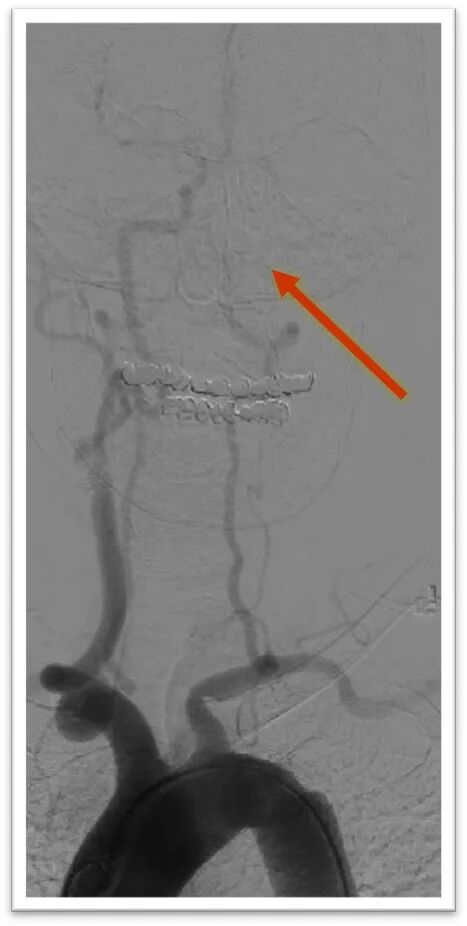

取栓后造影显示左侧颈内动脉血流恢复,管腔内局部可见白色血栓影,左侧颈外动脉闭塞,左侧大脑中动脉M2段上干长节段血栓影,下干闭塞,动脉缓慢推注替罗非班10ml,造影显示颈内动脉管腔通畅,大脑中动脉下干血流恢复,上下干仍可见血栓。

微导丝引导微导管顺利置于左侧大脑中动脉上干,半释放6-30mm支架,停留5分钟后完全取出血栓,造影显示左侧大脑中动脉血流完全恢复,mTICI:3级。